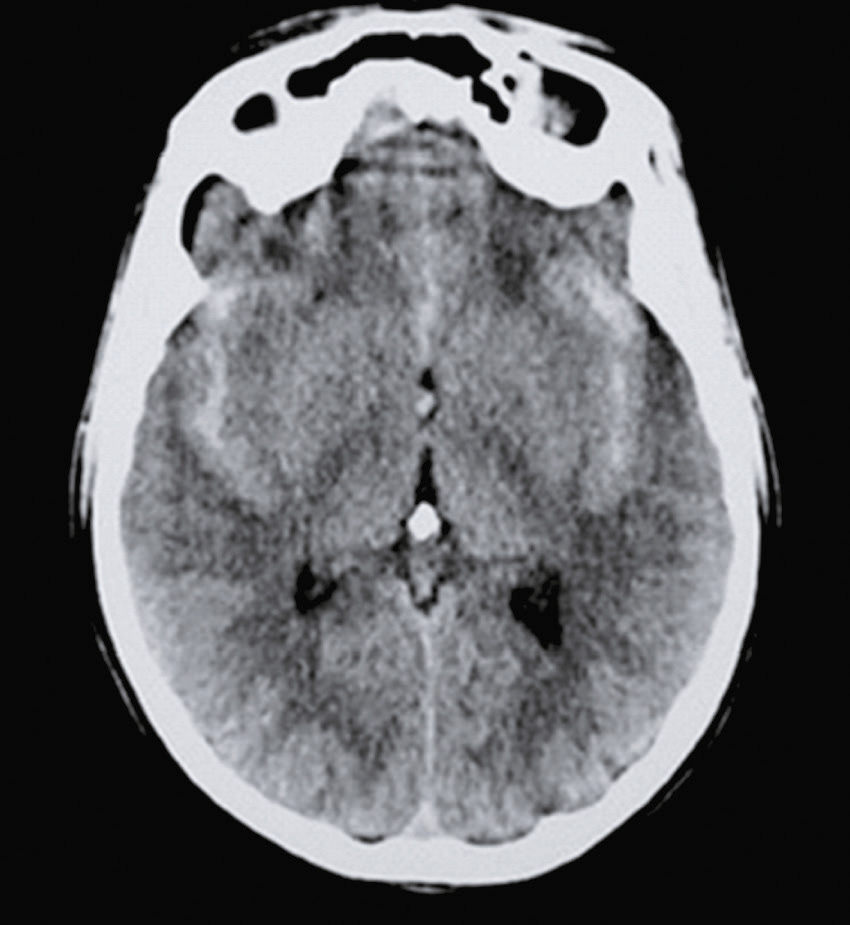

Vous débutez un traitement par benzodiazépine, vitaminothérapie B1, B6, PP, réhydratation par sérum salé et immunoglobulines polyvalentes intraveineuses associées à une héparine de bas poids moléculaire à dose isocoagulante. Le lendemain matin, le patient s’est aggravé d’un point de vue clinique. Il n’a plus d’hallucination visuelle mais il présente maintenant une tétraparésie évaluée à 3/5 avec ataxie des quatre membres, une dysarthrie, des troubles de la déglutition, et une ophtalmoplégie bilatérale. Un bilan biologique a été prélevé avant votre arrivée : numération formule sanguine : Hb : 13,8 g/dL, leucocytes : 8 600/ mm3, plaquettes : 332 000/mm3, ionogramme sanguin : Na+ : 142 mmol/L, K+ : 4,2 mmol/L, clairance de la créatininémie : 92 mL/min, glycémie : 5,8 mmol/L, transaminases, phosphatases alcalines, bilirubines et γ-GT normales, CRP : 3 mg/L.

Une IRM cérébrale a été également réalisée (fig. 31.4). Quelle est la séquence présentée ?

L'image montre une IRM (Imagerie par Résonance Magnétique) du cerveau humain en coupe axiale, c'est-à-dire une vue transversale du cerveau prise horizontalement. Cette image est particulièrement intéressante car elle permet de visualiser les structures internes du cerveau avec une grande précision. On peut observer les globes oculaires en haut de l'image, qui apparaissent comme deux cercles blancs. Les différentes zones du cerveau sont visibles, avec des variations de teintes qui indiquent les différentes densités des tissus cérébraux. La région centrale lumineuse correspond au tronc cérébral, une structure cruciale pour de nombreuses fonctions vitales. Les zones plus sombres autour du tronc cérébral représentent les hémisphères cérébraux. Cette image est utilisée pour diagnostiquer et évaluer diverses conditions neurologiques, telles que les tumeurs, les accidents vasculaires cérébraux, les infections, et les anomalies structurelles. L'IRM est une technique non invasive qui utilise des champs magnétiques et des ondes radio pour produire des images détaillées des organes et des tissus internes.

- A T1

- B écho de gradient

- C T2

- D T2/FLAIR

- E diffusion